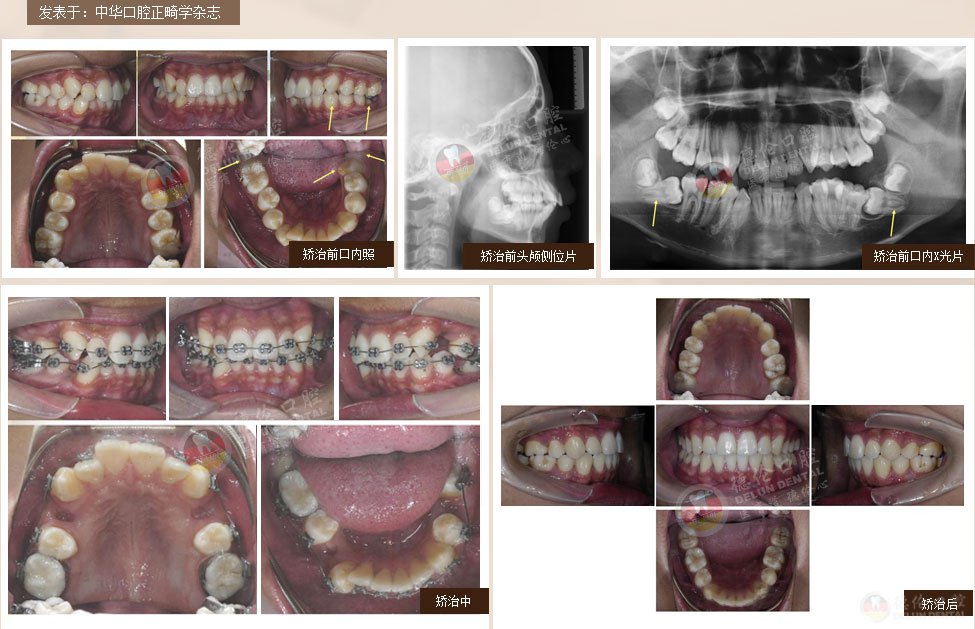

案例1:男 17岁

牙齿症状:下颌右侧第二、第三磨牙水平阻生,下颌左侧第三磨牙水平阻生

矫治方法:下颌拔除两颗第三磨牙(智慧齿)

案例2:女 24岁

牙齿症状:牙列不齐、下颌第二、第三磨牙水平阻生,左侧磨牙锁牙合

矫治方法:拔除上颌及右下第一双尖牙,左下第二双尖牙以及2个下第三磨牙